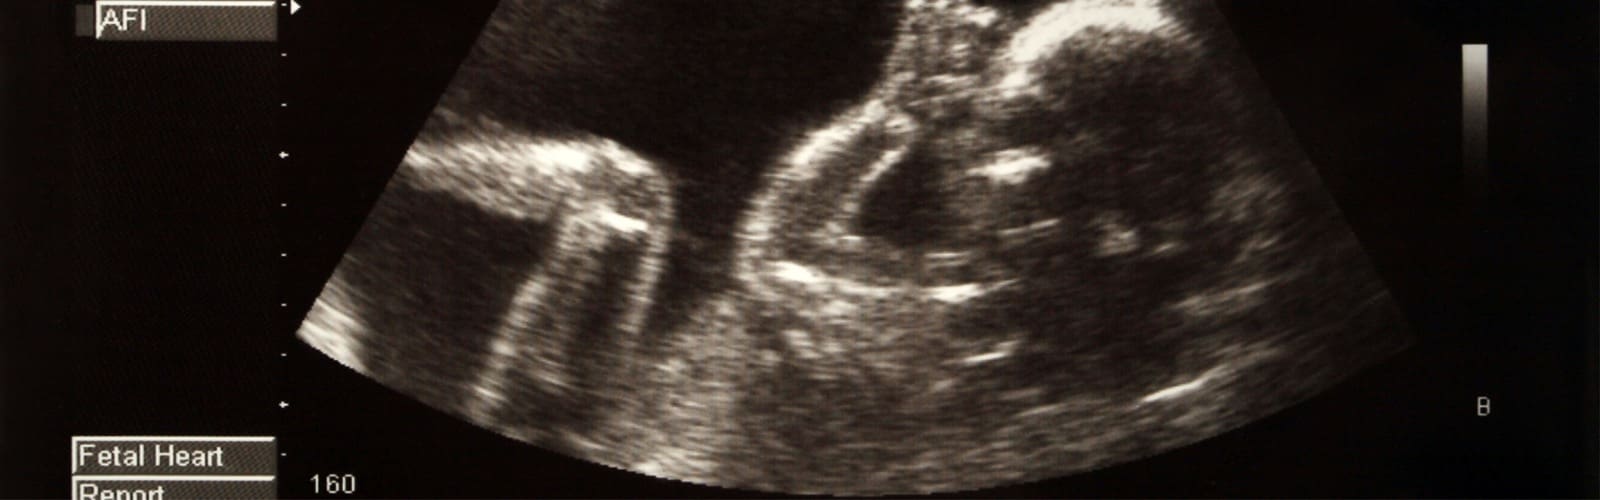

- Obstetrical Imaging

- Nuchal Lucency Evaluation

- First Trimester

- Second Trimester

- Third Trimester

- Biophysical Profile